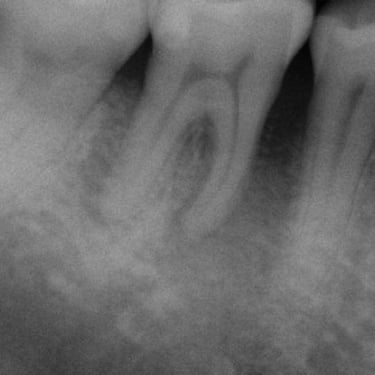

Reabsorción Interna

La reabsorción interna es la destrucción progresiva de la dentina desde el interior del diente hacia afuera, generalmente debido a un trauma o inflamación pulpar.

Los pacientes pueden notar un cambio de color en el diente.

Es necesario un tratamiento de conducto para detener el proceso y salvar el diente. Sin tratamiento, el diente puede debilitarse y fracturarse.